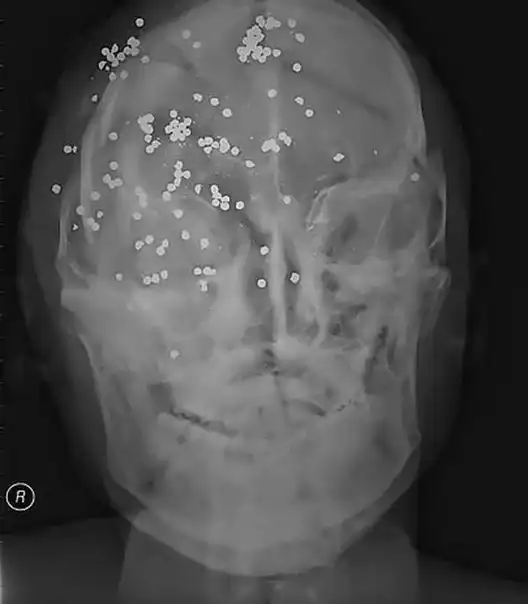

Убийство. Множественные выстрелы в голову.

Ранения дробью в голову.